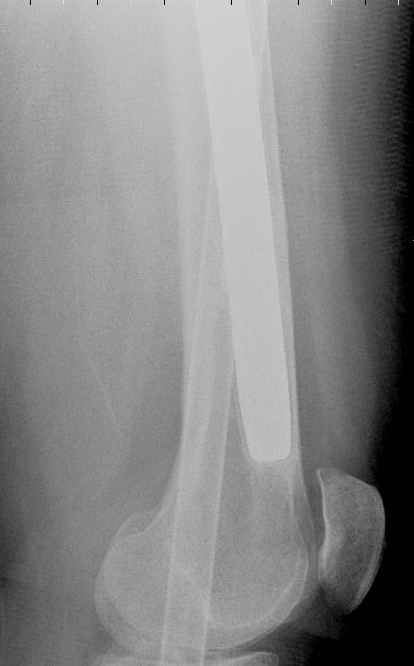

May I have some advice on the following case? Middle aged woman, No chronic medical problems, +tobacco use - but she promises she's going to quit! Original MVC in late 1990's, initial rod failed, and 2 subsequent exchanges failed (most recently shown in attached jpgs.)

Most recent one (6/2002) was apparently an open nailing to remove last broken nail, but no grafting was performed in conjunction. Now sent to me with broken 14mm R/T nail in place.WBC, Hgb, Chemistries normal.ESR 34CRP 4.2No other apparent locus of infection.I was considering a staged approach - removing nail and screws and obtaining cultures.If negative, proceed with exchange nailing with open grafting +/- BMP, But how best to deal with that pedestal distally and avoid anterior breech near patella? If positive cultures, what would be best option?Thanks. Tom Schaller Kalamazoo, MI.

I would 1)use a poller wire to push the distal tip more posterior than it is now, 2)use a nail with extended options of distal locking (3-4 screws) and/or use poller screws - probably for the proximal fragment too, 3)lock it statically for 8-10 weeks, then dynamize by removal of the proximal locking screw. Good initial stabilization and no dead space in the nail must be enough to control low grade infection if any.

In my opinion, there is no nail strong enough to tolerate a varus deformity of femur after nailing. The AP view of the distal femur shows that the femur has been repeatedly nailed in varus. The tip of the nail is short and lateral in distal lateral metaphysis. It should be central over the intercondylar notch and buried in the distal epiphyseal scar. This has resulted in constant bending forces on the nail (see the "windshield wiper" sign) and its eventual fatigue failure.